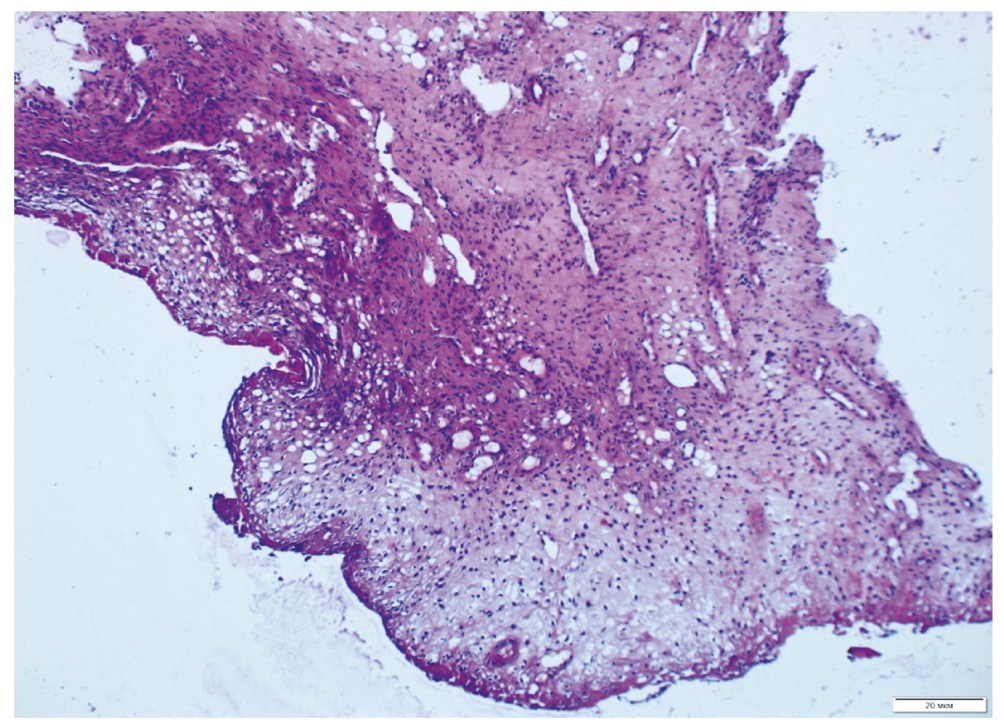

На 28-е сутки лечения с применением ВЧЭС в биоптатах ДЯ явно доминировали участки созревающей грануляционной ткани и зрелой соединительной ткани. Наблюдались выраженные регенераторные изменения покровного многослойного плоского эпителия (преимущественно с краёв) с явлениями акантоза и усилением неоангиогенеза капилляров (рис. 4).

Рис. 4. Биоптат ткани дна пролежня на 28-е сутки лечения с использованием высокочастотной электростимуляции. Окраска гематоксилином и эозином.

Fig. 4. Biopsy specimen of the bottom of the bedsore on the 28th day of treatment using high-frequency electrical stimulation. Stained with hematoxylin and eosin.

Созревающая грануляционная ткань замещала собой очаги фибриноидно-некротических изменений. В контрольной группе на фоне стандартной терапии морфологическая картина в те же сроки медленно и постепенно переходила в фазу структуризации: просматривались грануляции, однако более вялые и скудные, чем в основной группе. Отмечена очень слабая краевая эпителизация, сохранялись зоны некроза и микроциркуляторных расстройств (рис. 5).